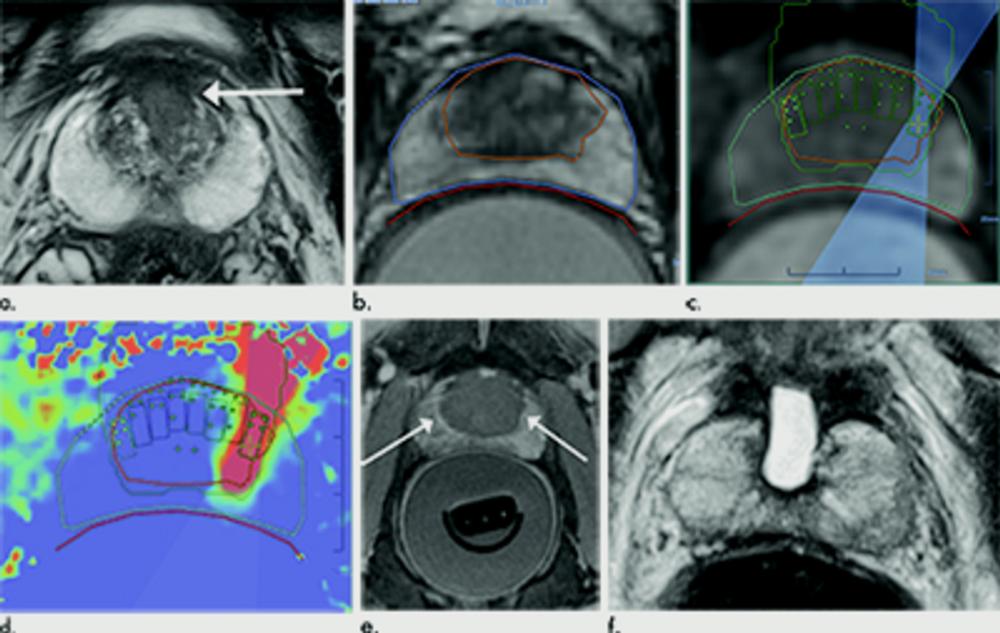

Figure 2. Images in 75-year-old man with biopsy-confirmed Gleason score 7 (4+3) prostate cancer. (a) Pretreatment axial T2-weighted fast spin-echo MRI scan on day of treatment (repetition time msec/echo time msec, 4416/81) shows tumor in left posteromedial peripheral zone at midgland (arrow). Endorectal treatment probe with degassed water is seen in rectum. (b) Intraoperative MRI scan shows contoured rectal wall (red line), prostate margin (blue outline), and region of interest (yellow outline). Because urethra was included in planned treatment volume, a suprapubic catheter was placed for continuous bladder drainage during treatment. (c) Intraoperative MRI scan shows focused ultrasound beam path (blue) overlaid on treatment plan. Rectangles illustrate each sonication spot. (d) Thermal map image obtained during treatment with heat deposition color coded in red overlaid on sonication spot. (e) Axial gadopentetate dimeglumine–enhanced subtraction MRI scan (200/5.4) obtained immediately after treatment shows devascularized ablated volume (arrow). Note that devascularized area does not extend into transition zone anteriorly. (f) Corresponding axial T2-weighted fast spin-echo MRI scan (4140/97) at 5 months after ablation shows scarring at ablation site (arrow). (g) Axial gadopentetate dimeglumine–enhanced subtraction MRI scan (5.39/1.88) does not show any early enhancement on dynamic contrast-enhanced images at treatment area (arrow). All six cores from treatment area, including margins, were negative for cancer at biopsy.